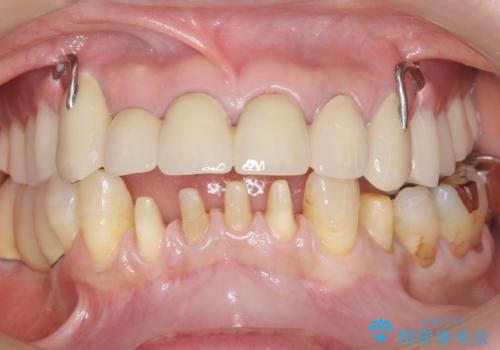

前歯がかけた、ぐらぐらする 60代女性

- 下の前歯が欠けてぐらぐらすることを主訴に来院された患者様です。

以前行った奥歯の治療により下顎前歯の動揺は改善傾向にあり顕著ではなかったのですが、欠けて黒くなっていることと少しの動揺が気になるとのことでした。

元気なうちに治療しておきたいという患者様の強いご希望により、下顎前歯の連結補綴と欠けている小臼歯の補綴治療を行いました。